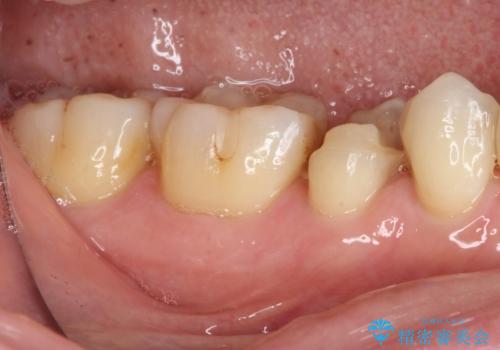

以前治療した詰め物が欠けた オールセラミッククラウンによる補綴

- 他院にて治療した詰め物が欠けてしまった事を主訴に来院された患者様です。

詰め物の範囲が大きく、部分的な詰め物では再び割れてしまうリスクが高いため、

オールセラミッククラウンにて補綴することとしました。

しみる症状はなくなり、見た目もきれいになり、とても満足されました。